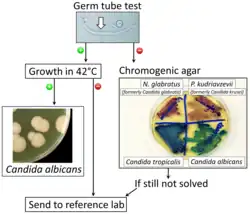

A United States study in 2022 showed that most cases of candidiasis are treated empirically (without culture, pending culture or by symptoms in cases where culture did not show candida), thus not knowing whether the subtype is Candida albicans or any other candida species.[94] For subtyping of candidiasis, a fungal culture can be performed, followed by a germ tube test in which a sample of fungal spores are suspended in animal serum and examined by microscopy for the detection of any germ tubes.[95] Colonies of white or cream color on fungal culture having a positive germ tube test is strongly indicative of Candida albicans.[95]

Chromogenic agar can help in indicating main species of Candida versus similar fungi. (CHROMAgar shown)

Chromogenic agar can help in indicating main species of Candida versus similar fungi. (CHROMAgar shown) -

Algorithm for the diagnosis of Candida albicans versus differential diagnoses

Algorithm for the diagnosis of Candida albicans versus differential diagnoses